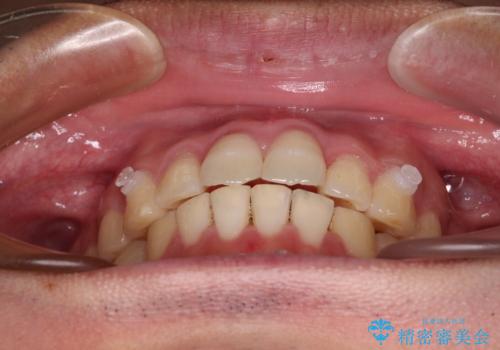

捻れて飛び出した前歯 インビザラインで整った前歯に

- 上下前歯のデコボコと、それに伴う出っ歯を気にして来院された患者様です。

インビザラインによる上下歯列の側方拡大と後方移動、IPR(歯と歯の間を削る)にるスペースの獲得により歯列を整えることとしました。